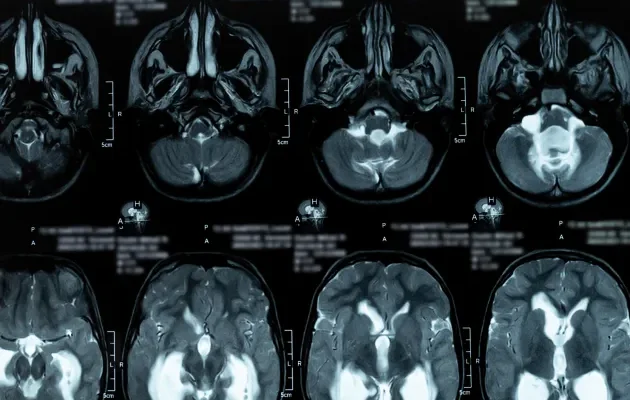

Hidrosefali Teşhisi Nasıl Konulur?

Anne Karnındaki Bebeklerde Fetal MR

Fetal hidrosefali teşhisi genellikle gebeliğin ikinci veya üçüncü trimesterinde konulur. Ultrason taramaları ile saptanan anormallikler, daha detaylı inceleme gerektirdiğinde fetal MR ile doğrulanabilir. Fetal MR, gelişmekte olan bebeğin beyin yapısını ve BOS akışını ayrıntılı olarak gösterir ve potansiyel hidrosefaliyi belirlemede etkili bir yöntemdir.

Yetişkinlerde MR BOS Akım

Yetişkinlerde ve büyük çocuklarda hidrosefali teşhisi için MR BOS Akım kullanılır. Bu teknik, BOS’un beyin ventriküllerinden nasıl akış gösterdiğini detaylı bir şekilde gösterir ve herhangi bir akış engeli veya anormalliği ortaya çıkarabilir. Bu görüntüleme yöntemi, hidrosefali varlığını doğrulamanın yanı sıra, teşhisin kesinleştirilmesi ve uygun tedavi planının yapılması için kritik bilgiler sağlar.